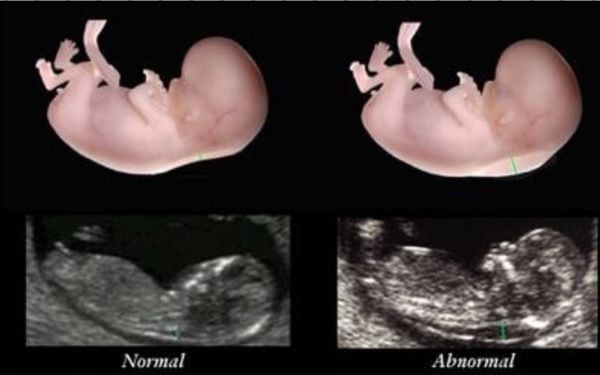

В конце первого триместра обычно имеется небольшое количество жидкости под кожей плода на затылке и шее. Эта жидкость называется затылочной прозрачностью (NT), и ее можно легко и точно измерить с точностью до десятой доли миллиметра.

При наличии избыточной жидкости и толщине NT, превышающей норму, существует связь с хромосомными аномалиями, такими как синдром Дауна, и некоторыми структурными аномалиями плода.

Не у всех детей с повышенным показателем NT есть синдром Дауна или какие-либо структурные аномалии.

Излишняя жидкость на затылке и шее обычно исчезает к 18 неделям. Жидкость сама по себе не является отклонением от нормы и не причиняет вреда ребенку, но может быть просто признаком потенциальной проблемы. Ребенка измеряют от головы до низа, чтобы определить длину от темени до крестца, и измеряют прозрачность воротникового пространства. Эти измерения вводятся в компьютерную программу вместе с датой рождения пациентки и биохимическим анализом крови в первом триместре. Затем компьютер вычисляет возрастной риск синдрома Дауна у пациентки и новый индивидуальный риск для этой беременности. Затем результаты обсуждаются с пациентом. Комбинированный результат NT предоставит пациенту оценку риска. Это будет либо высокий риск (риск выше 1 из 300), либо низкий риск (риск менее 1 из 300). Поскольку это скрининговый тест, а не диагностический тест, даже при низком расчетном риске синдром Дауна не исключен полностью и все еще может иногда возникать.

Это вызывает широкий спектр физических недостатков и трудностей в обучении. На данный момент до сих пор не существует полностью безопасного теста, который скажет вам, есть ли у вашего ребенка синдром Дауна или нет, но NHS предлагает всем комбинированный скрининг первого триместра, который проводится примерно в 12 недель с использованием сочетание результатов ультразвукового сканирования и базового анализа крови, чтобы оценить вероятность того, поражен ли ваш ребенок или нет. Ключевым ультразвуковым маркером на этом этапе является измерение воротникового пространства или пространства на задней части шеи ребенка.

На этом этапе развития ребенка нормально, если некоторое количество жидкости скапливается в этом месте на задней части шеи ребенка — это случается с каждым ребенком, поэтому небольшое количество жидкости совершенно нормально, но у ребенка с проблемами часто сохраняется больше жидкости и измерение воротникового пространства увеличивается. Помимо того, что это хороший маркер для детей с синдромом Дауна, повышенное измерение воротникового пространства может также выявить другие генетические состояния, такие как синдром Эдвардса (когда у ребенка есть дополнительная копия хромосомы 18) и синдром Патау (дополнительная копия). хромосомы 13) и некоторые другие структурные проблемы, включая сердечные аномалии.